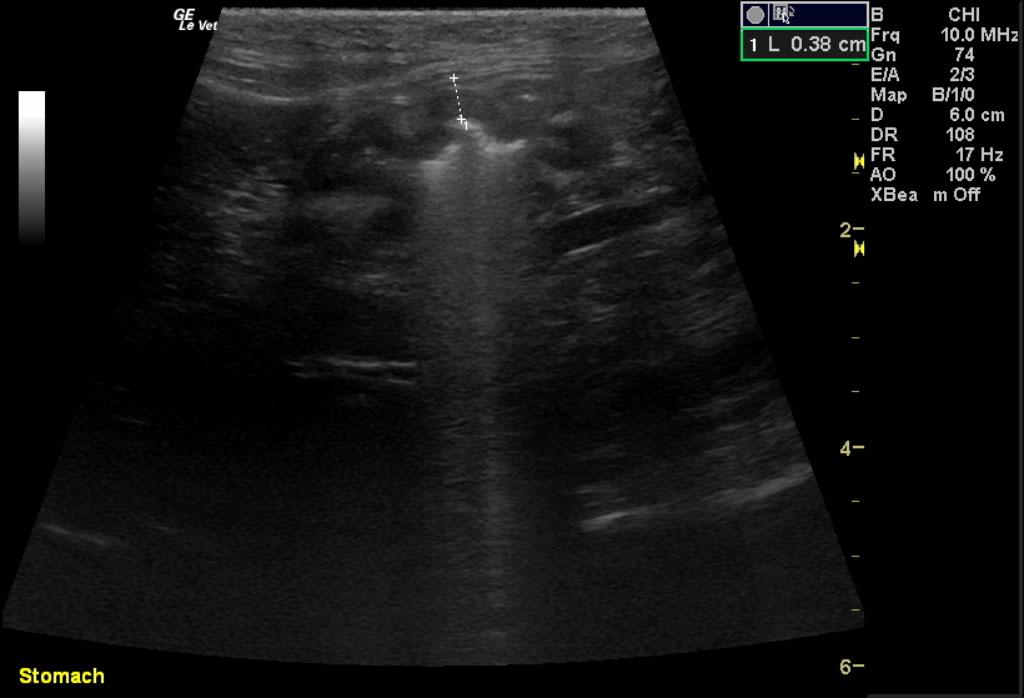

Image 1 & Video 1: The liver was moderately enlarged, rounded in shape having mildly hypoechoic echogenicity with multifocal hypoechoic and cystic nodules throughout. The gallbladder was normal in size, shape, and clean. Images 2-4 & Video 2-4: The left and right kidneys were severely enlarged with mild hydronephrosis in the right kidney. Both kidneys had hyperechoic cortices with large hypoechoic caps surrounding and invading the renal cortices (left kidney cap-7.4 mm in thickness, right kidney cap-13.6 mm in thickness). Image 5 & Video 5: Stomach: mucosal layer is mild/moderately thickened with overall wall thickness measuring 3.8 mm. Images 6: Intestine: there is focal mucosal layer thickening measuring up to 5.1 mm while the rest of the intestinal loops are of normal thickness. Video 6: Colon: the colonic wall appeared thickened at the ileocecolcolic junction. Image 7: Lymph Nodes: Multiple mesenteric lymph nodes were severely enlarged throughout the abdomen. The epigastric LN enlargement is shown in this image in the near field.